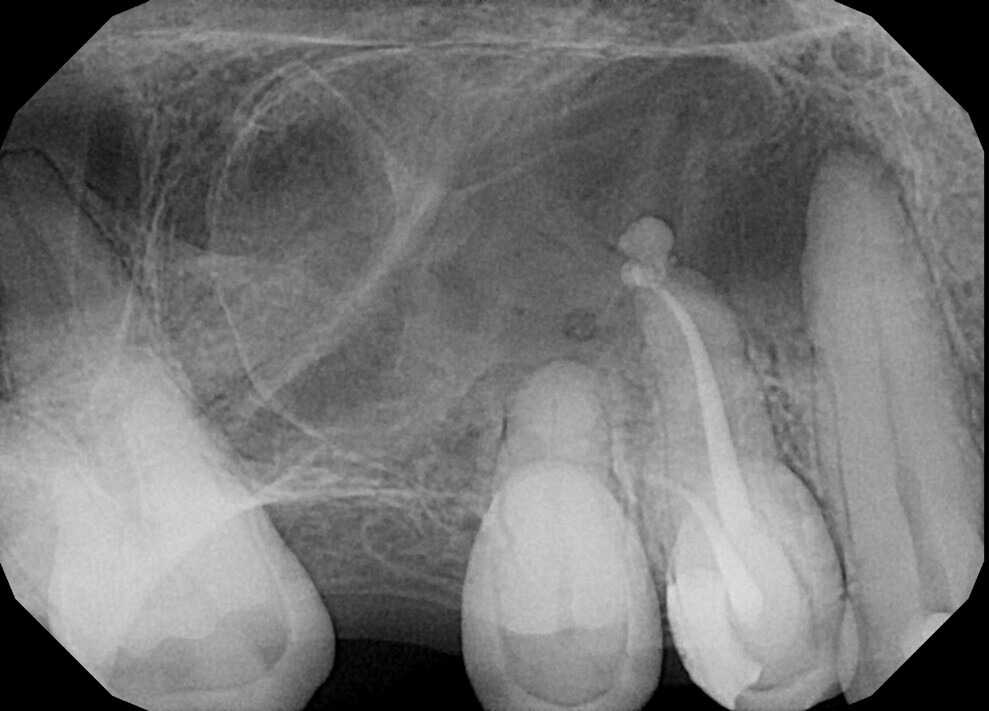

Fig.: 19

A 56-year-old patient was referred to our clinic for endodontic treatment of tooth #15. The initial radiograph showed a complex anatomy with abrupt curvatures (Fig. 19). In such cases, our main goal is to avoid breaking the instrument. The in–out technique is a good choice in these situations too. After isolation, the access cavity was created (Fig. 20). Owing to abrupt curvatures in both canals located, a glide path was achieved with manual ISO #8, 10 and 12 K-files (VDW; Fig. 21). During manual instrumentation, small adjustments to the access cavity were made with an ultrasonic tip (Fig. 22).

After manual glide path preparation, final instrumentation with VDW.ROTATE files was performed using the in–out technique (Fig. 23). After preparation and final irrigation, obturation was performed with the continuous wave compaction technique and 2Seal, a root canal sealer on an epoxy–amine resin basis (VDW; Fig. 24). The final radiograph showed the fully obturated root canal complex (Fig. 25).